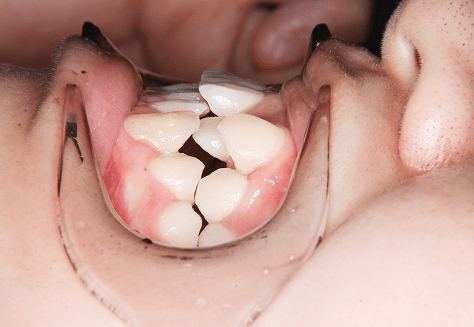

M.H

治療前

治療後

主訴

前歯が出ている。下の歯並びが特に気になる。奥歯でしっかり噛めない。

診断

上顎前突・叢生・シザーズバイト

年齢/性別

20代/男性

抜歯部位

下顎両側大三大臼歯(口腔外科にて)

上顎両側第一小臼歯・下顎左側側切歯

(当院にて5,500円×3) -

使用装置

上下エッジワイズ→インビザライン(PBM使用)

保定装置

上下ビベラリテーナー

基本料金

880,000円

診察料金

5,500円×44回

治療期間

3年6カ月